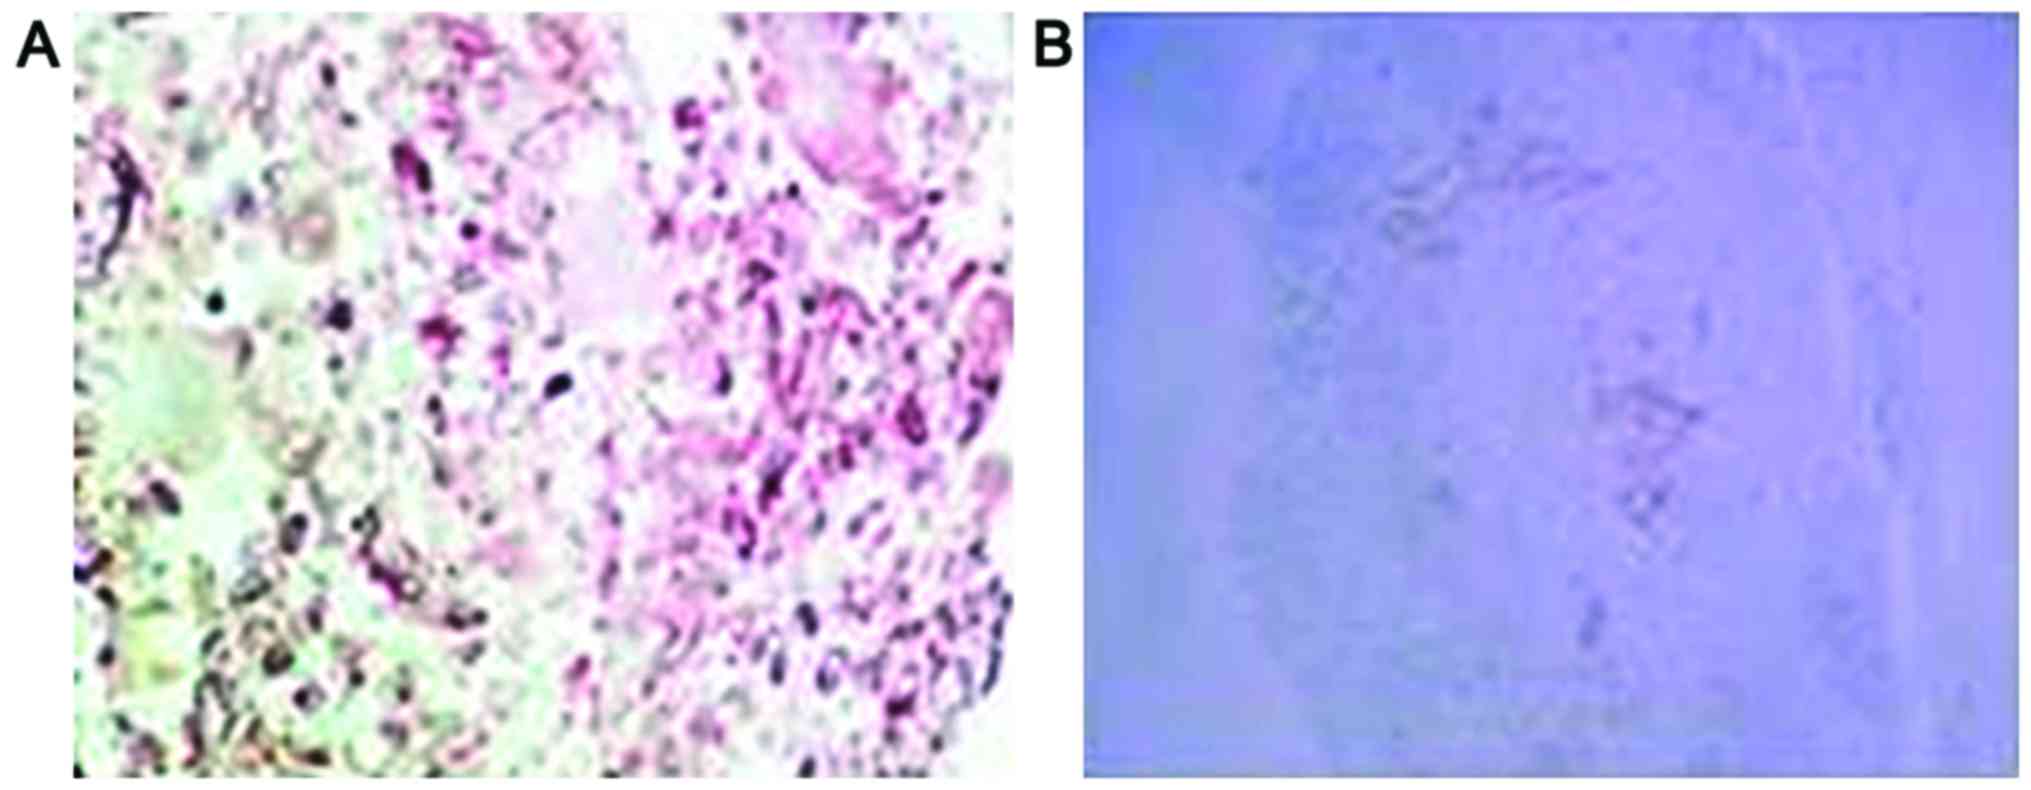

Positive staining for p-AKT and HSP70 proteins

manifested as purple particles in the cytoplasm (Figs. 4 and 5).

The positive expression rate of p-AKT in osteosarcoma cells was

13.3% (4 of 30 cases), which was significantly lower than the 73.3%

found before chemotherapy (22 of 30 cases, p<0.05). After

chemotherapy, the positive expression rate of HSP70 in osteosarcoma

cells was 6.7% (2 of 30 cases), which was significantly lower than

the 83.3% found before chemotherapy (25 of 30 cases, P<0.05)

(Table III).